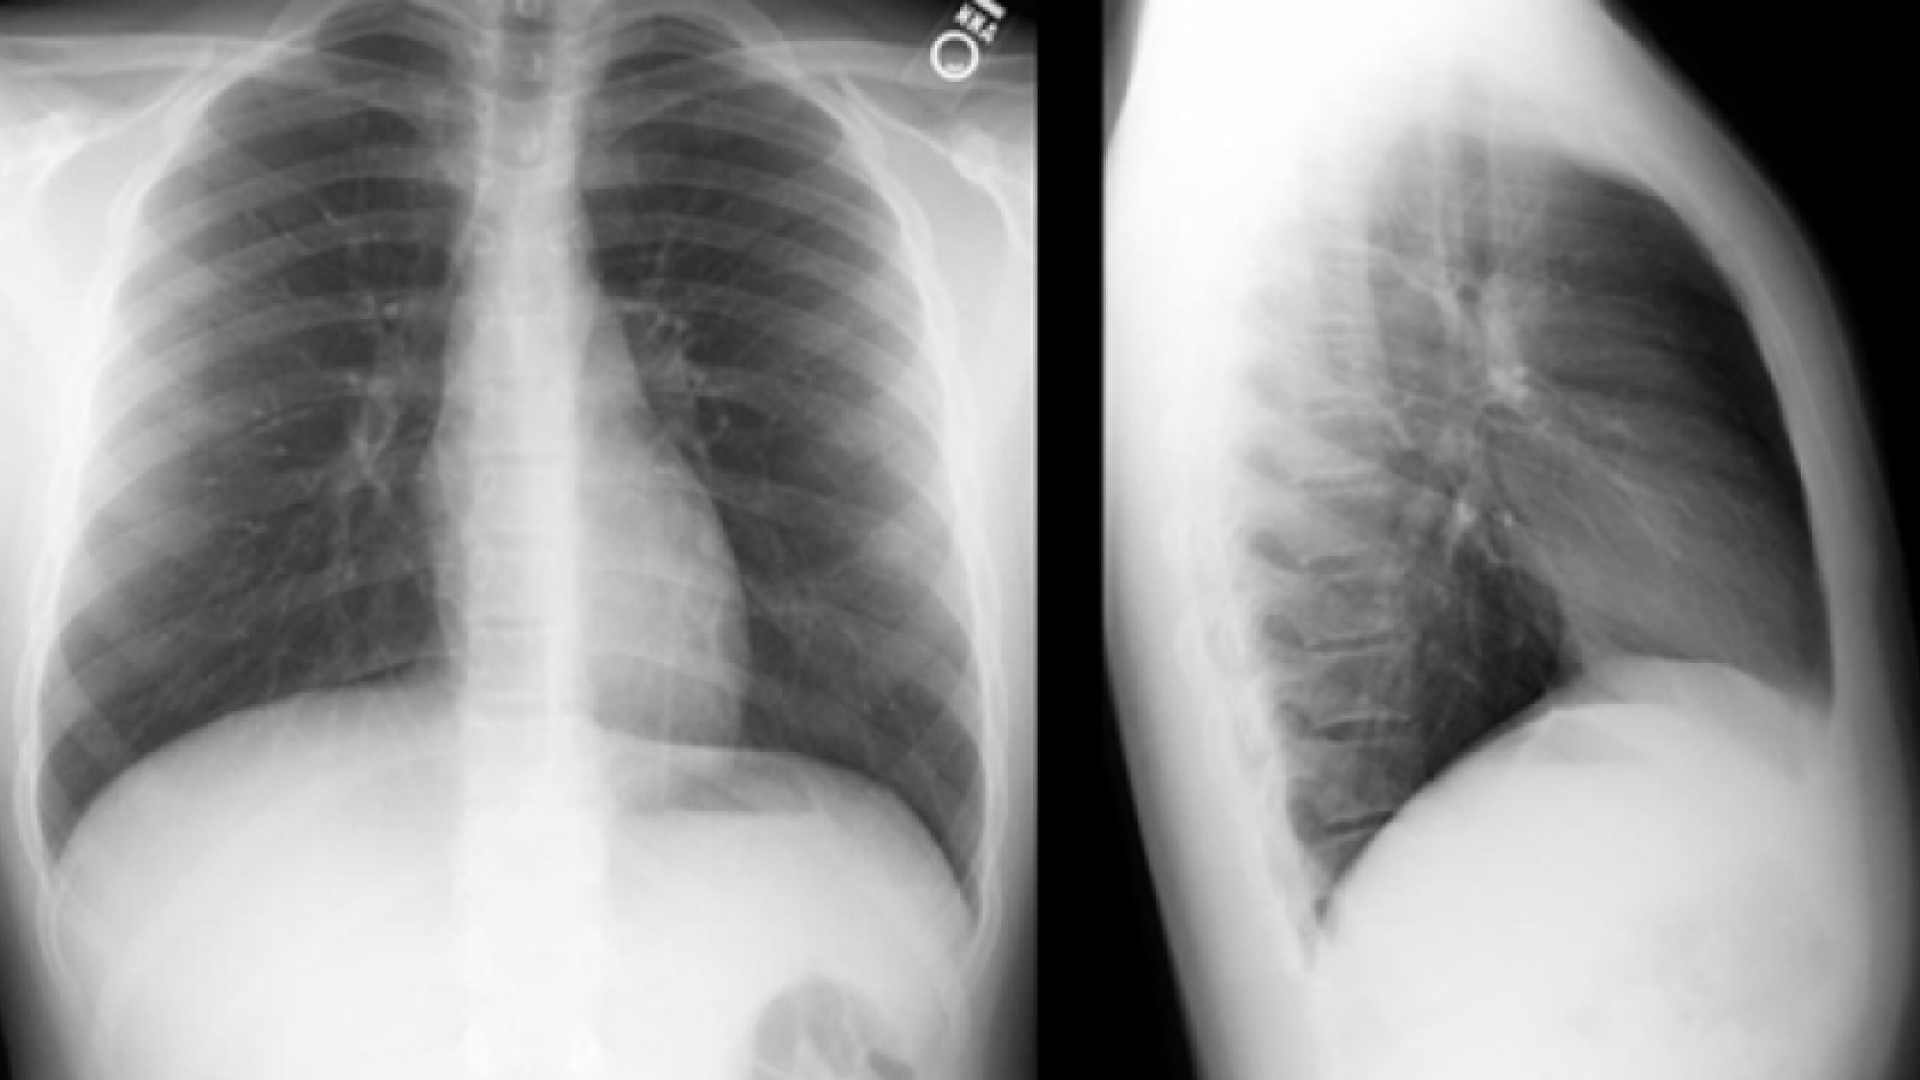

Emergency room 1

Description

You need to find the diagnosis. First, analyze the picture and the different elements that are given to you. Take a paper and note down all the clues and arguments that will lead you to the right diagnosis. When you are finished, start a debate with the colleague of your choice in the next section!